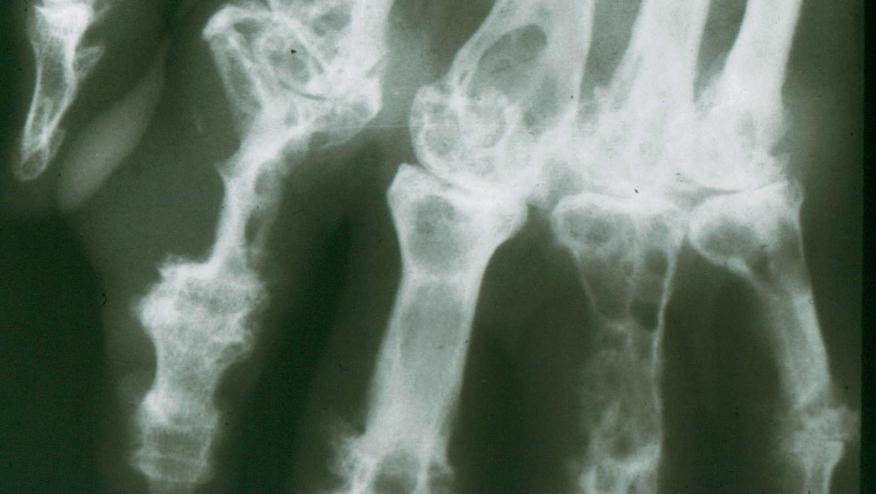

Image credit: "Fluorescent uric acid" by Bobjgalindo - Own work. Licensed under GFDL via Wikimedia Commons.